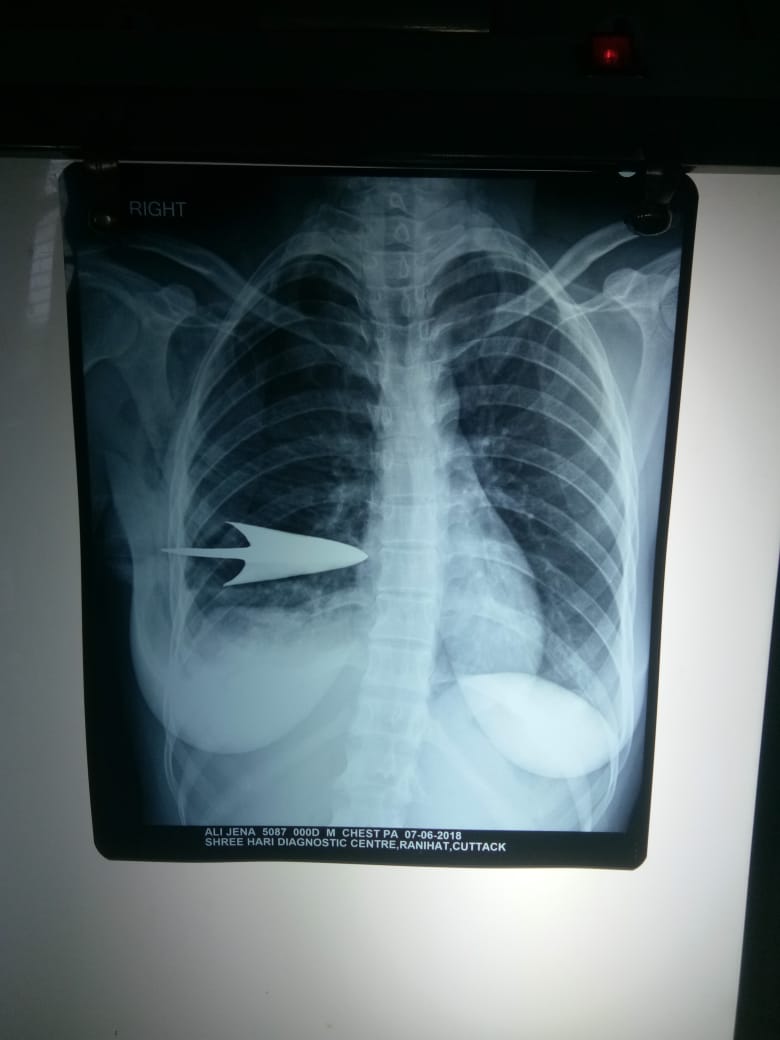

Arrow removed from woman’s body

Cuttack: A four-member doctors’ team of the SCB Medical College and Hospital (SCBMCH) here Thursday successfully removed an arrow that pierced the body of a woman hailing from Kathapala in Keonjhar district.The woman identified as Ali Jena was shot with an arrow over some dispute with a youth of the same village under Ghasipura police limits. She was initially rushed to the nearby Anandapur hospital and later shifted to SCBMCH casualty ward after her condition worsened.“The patient was provided with necessary treatment prior to the surgery. The arrow was operated out from her body after four hours of ordeal,” said surgery department head Manoj Patnaik.